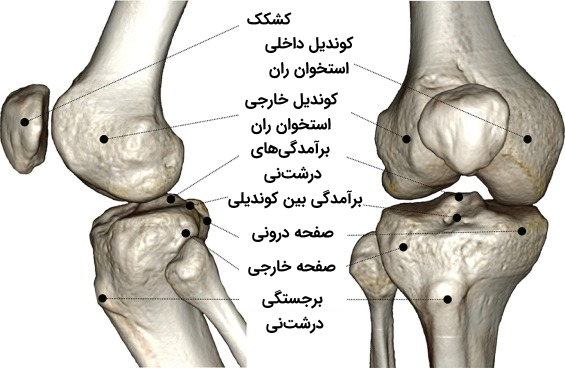

در انتهای استخوان ران دو سطح مفصلی گرد وجود دارند که به آن «کوندیل» (Condyle) میگوییم. کوندیلهای استخوان ران در مقابل دو سطح مفصلی روی استخوان درشتنی قرار دارند که به نسبت صاف به نظر میرسد اما در حقیقت اندکی مقعر است. رباطهای صلیبی که یکی از انواع رباطهای مفصل زانو هستند از فاصله بین دو کوندیل میگذرند و به دو برجستگی کوچک متصل میشوند که بین کوندیلهای استخوان ران و استخوان درشت نی قرار دارند.

مفصل تیبیوفمورال

«مفصل تیبیوفمورال» (Tibiofemoral Joint) مفصلی است که بین کوندیلهای داخلی و خارجی انتهای دیستال فمور (استخوان ران) و «صفحههای تیبیا» (Tibial Plateaus) قرار دارد. سطح هر دو استخوان شرکت کننده در این ساختار با لایهای ضخیم از غضروف هیالین پوشیده شده است.

کوندیلهای داخلی و خارجی دو برآمدگی استخوانی با سطحی محدب و صاف هستند که در انتهای دیستال فمور قرار دارند. این دو کوندیل در بخش عقبی توسط شیاری عمیق به نام «حفره بینکوندیلی» (Intercondylar Fossa) از یکدیگر جدا شدهاند «کوندیل داخلی» (Medial Condyle) بزرگتر، باریکتر و برجستهتر از کوندیل خارجی است. تفاوت اندازه بین این دو کوندیل باعث ایجاد زاویهای بین فمور و درشت نی یا «تیبیا» (Tibia) میشود. سطوح خارجی کوندیلها را که ظاهری زبر دارند، با عناوین «اپیکوندیل خارجی» و «اپیکوندیل داخلی» میشناسیم.

صفحههای تیبیا سطوح فوقانی کوندیلها هستند که یکی از ویژگیهای خاص آنها این است که کمی مقعر هستند. این دو صفحه در انتهای پرگزیمال تیبیا یا درشتنی قرار دارند و توسط برآمدگی استخوانی از یکدیگر جدا میشوند که آن را با نام «برآمدگی بینکوندیلی» (Intercondylar Eminence) میشناسیم. سطوح داخلی مفصل درشتنی ظاهی بیضیشکل دارد، اما سطح مفصل خارجی ظاهری کرویتر دارد.

مفصل پاتلوفمورال

«مفصل پاتلوفمورال» (Patellofemoral Joint) یک مفصل مسطح است که به دلیل اتصال سطح کشککی استخوان ران به سطح پشتی استخوان کشکک ایجاد شده است. سطح کشککی استخوان ران در اصل یک شیار در قسمت جلویی انتهای استخوان ران است که به سمت پشت ادامه مییابد تا به داخل حفره موجود میان کوندیلها برسد. «کشکک» (patella) استخوانی مثلثیشکل است که بخشهای تحتانی و راسی آن ظاهری متفاوت دارند.

استخوان کشکک در اصل از دسته استخوانهای کنجدی یا «استخوانهای سزاموئید» (Sesamoid Bones) است. استخوانهای کنجدی، استخوانهایی کوچک هستند که در نزدیکی سطوح مفصل در میان یک ماهیچه یا تاندون قرار دارند. با توجه به این ویژگی باید بگوییم که استخوان کشکک درون تاندون ماهیچه چهارسر ران جا گرفته است و محکم در جای خود نگه داشته شده است. در بخش انتهایی یا دیستال کشکک، شاهد گسترش یافتگی تاندون چهارسر راه هستیم که در نهایت نوار مرکزی محکمی به نام «رباط کشککی» را میسازد.